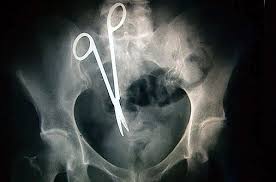

O Şişe Oraya Bakın Nasıl Girmiş…Röntgen filmlerinden çıkan akılalmaz şeyler Röntgen filmlerinden “akıl almaz şeyler Hastane koridorlarına düşenler bilir…